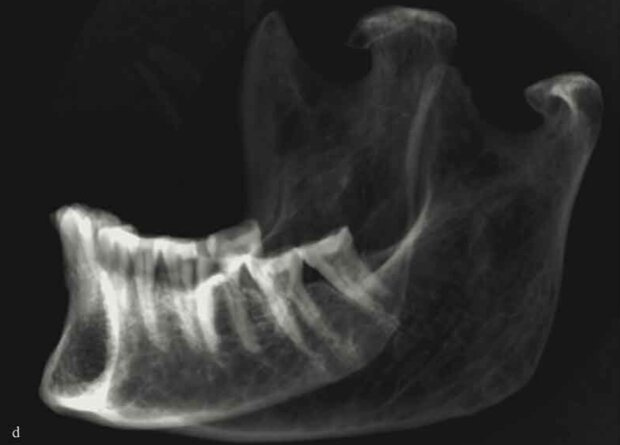

Палеопатологи исследовали две египетские мумии времен XVIII и XXII династий, которые были обнаружены в «Долине Царей». Они принадлежали двум женщинам из знатных семей, которых похоронили в общей скальной гробнице с разницей примерно в 500 лет. Одна из мумий молодой девушки оказалась отличной сохранности, но ученым не удалось найти у нее никаких серьезных патологий или травм. Вторая же находка оказалась повреждена еще в древности, однако на рентгенограммах исследователи обнаружили, что эта взрослая женщина, похоже, страдала от псориатического артрита. Об этом сообщается в статье, опубликованной в Scandinavian Journal of Rheumatology.

Развитие методов палеорадиологии позволило существенно продвинуться в изучении биоархеологических материалов. Так, для исследования древних мумий в распоряжении ученых оказались современные методы визуализации — компьютерной и магнитно-резонансной томографии, рентгенографии и трехмерной реконструкции. Дело в том, что традиционное патолого-анатомическое изучение мумифицированных тканей не только приводит к порче важных находок, но и физически трудно выполнимо из-за сухости и жесткости таких останков. Напротив, палеорадиология позволяет находить следы отправления тяжелыми металлами и свидетельства гнойных инфекций, а также установить причину смерти, как это произошло, например, с Этци (подробнее о нем можно прочитать в нашем материале «Из пропасти во льду»).